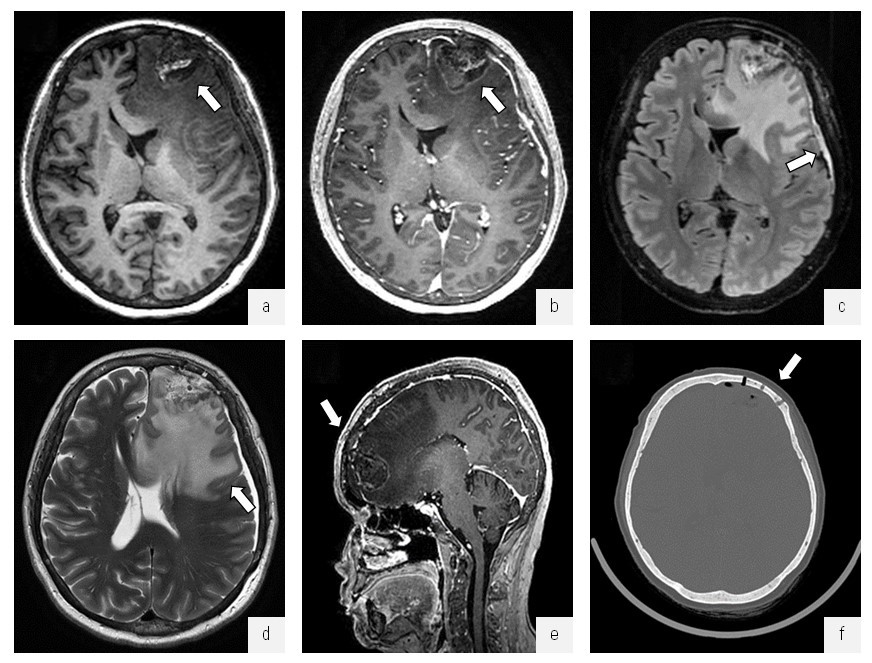

Операция 25.08.2022: микрохирургическое удаление опухоли левой лобной доли с применением нейрофизиологического мониторинга. Удаление образования кожи волосистой части головы в лобной области. Весь удаленный материал отправлен на прижизненное патологоанатомическое исследование. Состояние пациентки после операции стабильное. По контролю МРТ ГМ состояние после костно-пластической трепанации черепа в левой лобной области по поводу оперативного удаления опухоли левой лобной доли с признаками выраженного вазогенного отека в левых лобной и островковой долях с распространением на мозолистое тело и формированием участка гипоперфузии латерально от полости. Дислокация срединных структур вправо до 0,5 см. Вклинение левой поясной извилины под фалькс. Хроническая субдуральная гематома слева. Пневмоцефалия (рис. 3).

Рис. 3. МРТ и КТ головного мозга. Опухоль левой лобной доли, состояние после хирургического удаления опухоли: a — МРТ в режиме IR-FSPGR в аксиальной проекции, отмечается постоперационная полость (стрелка), выполненная ликворным и геморрагическим содержимым; б — МРТ в режиме IR-FSPGR с контрастным усилением в аксиальной проекции, отмечается умеренное, неравномерное накопление контрастного препарата по периферии послеоперационной полости (стрелка); в — МРТ в режиме Т2-FLAIR в аксиальной проекции, субдурально определяется серповидный участок повышенного относительно ликвора МР-сигнала толщиной до 0,7 см; г — МРТ в режиме Т2 в аксиальной проекции, отмечается распространенная зона вазогенного отека вещества головного мозга левого полушария с признаками дислокации срединных структур и боковых желудочков; д — МРТ в режиме IR-FSPGR с контрастным усилением в сагиттальной проекции; е — КТ головного мозга, костный режим, определяется зона оперативного доступа (стрелка), костный лоскут располагается ровно

Fig. 3. MRI and CT of the brain. Tumor of the left frontal lobe, a condition after surgical removal of the tumor: a — MRI in IR-FSPGR mode in axial projection, there is a postoperative cavity (arrow) made with cerebrospinal fluid and hemorrhagic contents; б — MRI in the IR-FSPGR mode with contrast enhancement in the axial projection, there is a moderate, uneven accumulation of contrast agent along the periphery of the postoperative cavity (arrow); в — MRI in T2-FLAIR mode in axial projection, subdurally determined sickle-shaped area of increased relative to the cerebrospinal fluid MR signal thickness up to 0.7 cm; г — MRI in T2 mode in axial projection, there is a common area of vasogenic edema of the brain substance of the left hemisphere with signs of dislocation of median structures and lateral ventricles; д — MRI in IR-FSPGR mode with contrast enhancement in sagittal projection; е — CT of the brain, bone mode, the zone of operative access is determined (arrow) the bone flap is located exactly